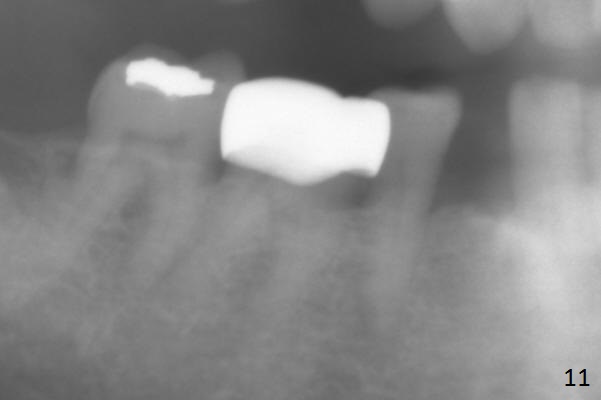

Preop exam shows posterior occlusal collapse (Fig.1) with #3 lost crown and #4 residual root. There is no ridge atrophy at #2 buccopalatally (Fig.2). The root stump of the tooth #4 is oblong, apparently consisting of 2 roots (Fig.3). There is a pointed septum at #4 socket (Fig.4, severe palatal wear of the anterior teeth (^)). After the septum is flattened with surgical handpiece and #8 round bur, 1.6 mm drill is used to start osteotomy in the septum, followed by Magic Drills (MD) and Magic Expanders (ME) alternatively. Osteotomy at #2 is initiated with Magic split, followed by MD and ME in the same manner. Dummy implants are tried in (Fig.5). Because of limited vertical height, Magicore (5.5x9(1) mm) is placed at #2, while a 4x13 mm FC implant 1-2 mm deeper than usual at #4 (Fig.6, ~ 55 Ncm). When a 5x4(2) mm pair abutment is placed at #4, there is no clearance between the Magicore at #2 and the abutment and the opposing dentition. A splinted provisional is fabricated at #3 and 4 to increase the posterior vertical height (Fig.7 P,8). In fact the occlusal contact is confined to the portion of the provisional at #3. The provisional has to extend to #4 to keep bone graft (Fig.6 *) and collagen plug in place. Liquid food is recommended at least 2-3 weeks, since there is no functional occlusal contact on the left. When the wound heals at #4 approximately 2-3 weeks, the splinted provisional can be sectioned with removal the portion at #4 to reduce micro-movement. By the evening the patient is doing well without nasal hemorrhage (sinus lift at #2 (Fig.6 *) or TMJ disturbance (due to increased vertical height).